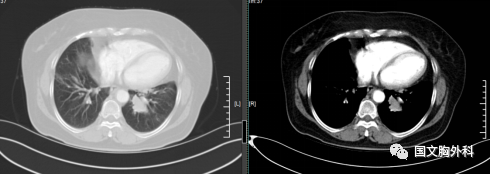

因病灶位置關(guān)系經(jīng)過(guò)支氣管鏡檢查未能明確病理,病灶包裹著血管CT穿刺風(fēng)險(xiǎn)巨大。